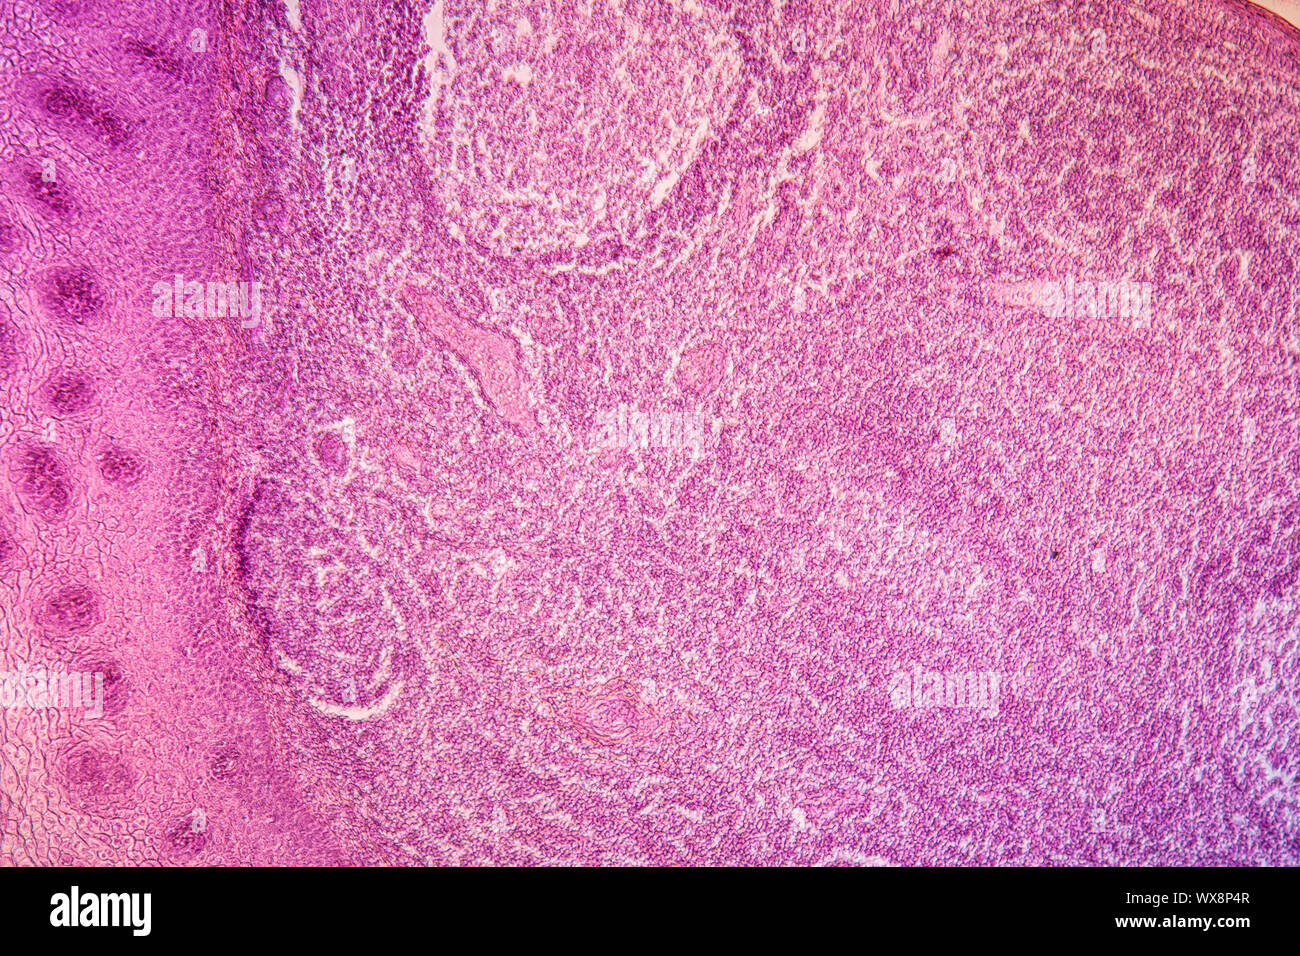

Mandelentzündung krankes Gewebe 100x Stockfotohttps://www.alamy.de/image-license-details/?v=1https://www.alamy.de/mandelentzundung-krankes-gewebe-100x-image274329575.html

Mandelentzündung krankes Gewebe 100x Stockfotohttps://www.alamy.de/image-license-details/?v=1https://www.alamy.de/mandelentzundung-krankes-gewebe-100x-image274329575.htmlRMWX8P4R–Mandelentzündung krankes Gewebe 100x